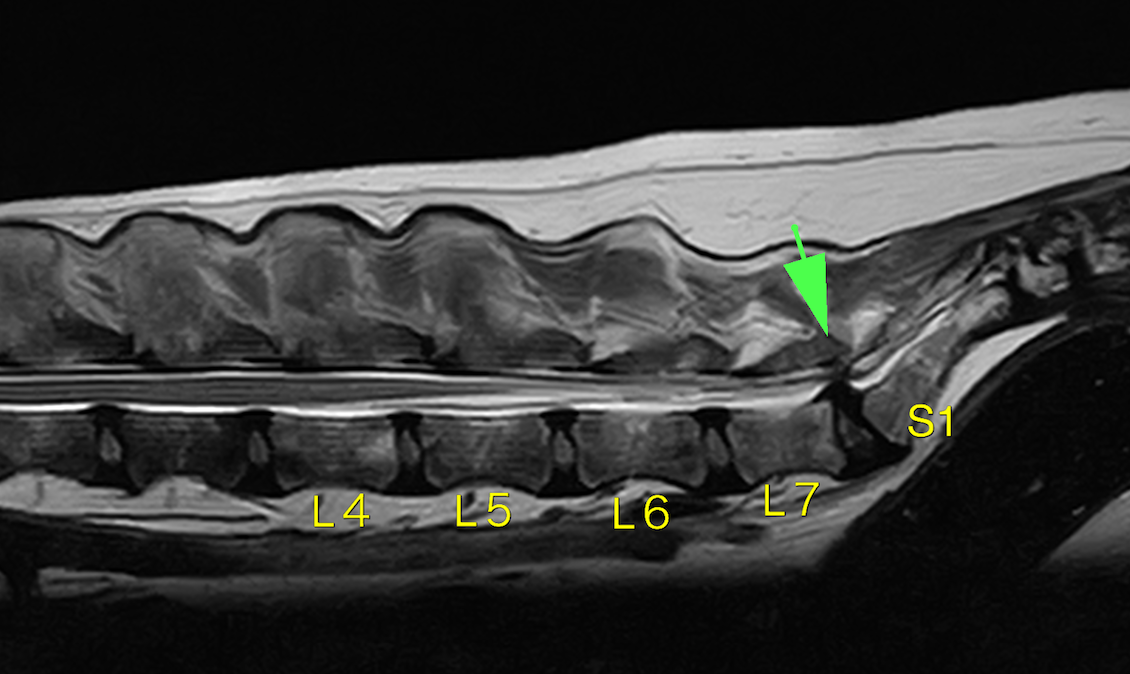

L7とS1(第7腰椎と仙骨)の部分での神経圧迫が確認できました。

L7-S1の間に圧迫が見られます。

矢頭部が圧迫物質です(黄色靭帯の肥厚がメイン)。